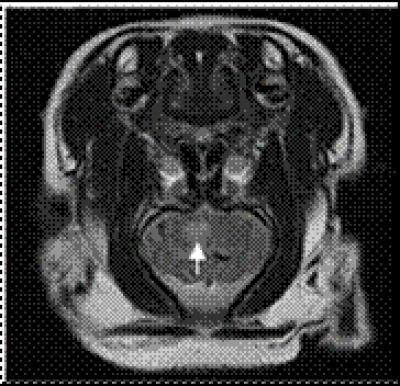

Conventional MRI showed evidence of infarction foci in the basal ganglia of miniature pigs undergoing occlusion of the rete mirabile with sodium alginate microspheres for 1 week.

(Photo Credit: Neural Regeneration Research)